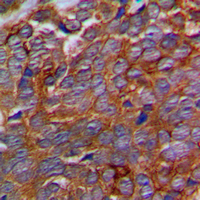

IHC (Immunohiostchemistry)

(Immunohistochemical analysis of p311 staining in human prostate cancer formalin fixed paraffin embedded tissue section. The section was pre-treated using heat mediated antigen retrieval with sodium citrate buffer (pH 6.0). The section was then incubated with the antibody at room temperature and detected using an HRP conjugated compact polymer system. DAB was used as the chromogen. The section was then counterstained with haematoxylin and mounted with DPX.)